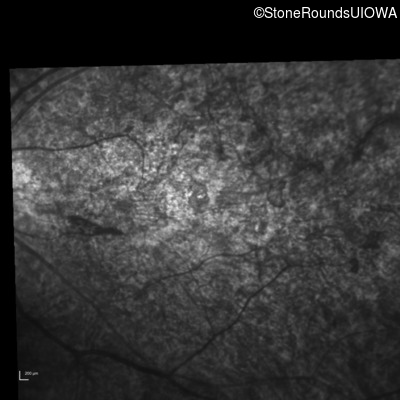

Infrared Fundus Photograph - Right - 20/400 sc

Exemplar